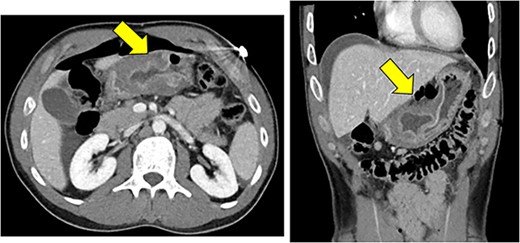

On presentation, the patient was afebrile with stable vital signs other than mild tachycardia with a heart rate of 110 beats per minute. Blood work showed a leukocytosis of 12.6 K/mcL. Basic metabolic panel was unremarkable. Physical exam showed diffusely tender abdomen with guarding. A CT scan demonstrated marked thickening of gastric antrum with perforation along the anterior wall with pneumoperitoneum and free fluid, consistent with a perforated gastric ulcer (Fig. 1). The patient was taken emergently to the operating room for diagnostic laparoscopy.

Significant mural thickening of gastric antrum with pneumoperitoneum along the anterior, superior wall, and free fluid around the liver, consistent with a perforated gastric ulcer.